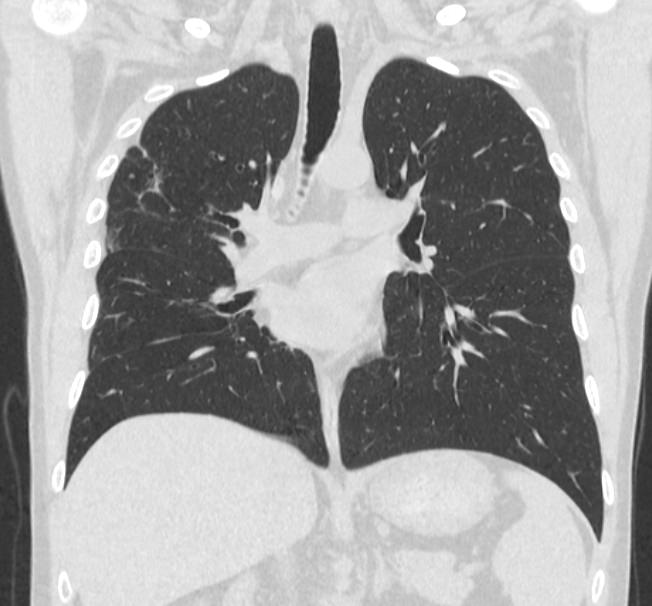

Во время исследования рентгеновская трубка томографа вращается вокруг исследуемой области и производит множество послойных снимков с шагом 0,5-1 мм. Полученные снимки поперечного сечения с помощью компьютерной программы могут быть преобразованы в 3D-изображения исследуемого органа или участка ткани. Это позволяет выявлять практически все заболевания легких на ранних стадиях и назначать своевременное лечение.

В медицинском центре «Доступная медицина» используется современный 128-срезовый компьютерный томограф TOSHIBA AQUILION CXL, на котором проводится сканирование легочной ткани. За счет увеличенного количества детекторов аппарат производит снимки с большой скоростью и минимальной дозой облучения. При этом инновационные цифровые приложения позволяют получить объемные изображения легочной ткани высокой четкости, контрастности и в мельчайших подробностях.